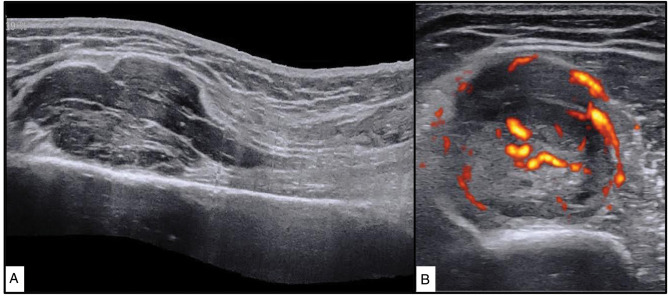

Intra-neural Ewing sarcoma is an extremely rare tumour and only a few isolated case reports exist in the literature. A 32-year-old South Asian male presented with wrist and finger drops of 3 months duration. Further evaluation with ultrasonography and magnetic resonance imaging revealed a tumour of the radial nerve in the arm. A wide excision of the tumour was performed, and the radial nerve was reconstructed with cabled nerve grafts. A diagnosis of extra-osseous Ewing sarcoma (EES) was made after histopathological evaluation using immunohistochemistry techniques. The patient subsequently received chemotherapy and after 5 months, he is disease-free and pain-free. However, there has been no motor recovery yet. Clinical findings and imaging can help and characterise the tumour, but histopathology and analysis for EWSR1 gene rearrangement are essential to confirm the diagnosis. Wide surgical excision and chemotherapy are the mainstay of managing neural EES.